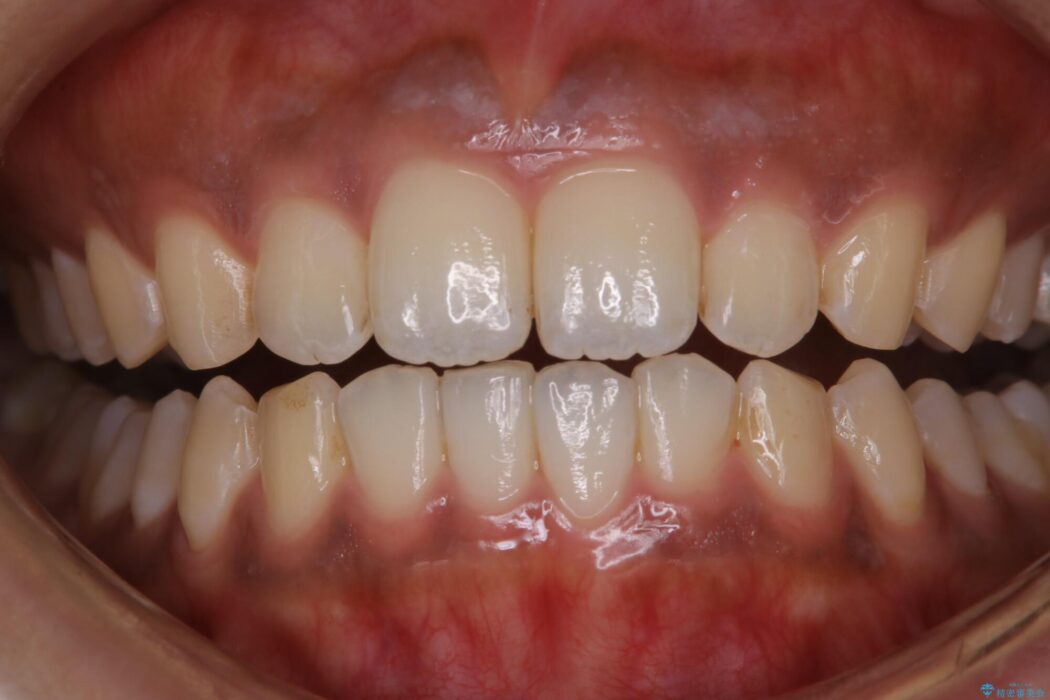

タバコに含まれているタールが歯の黄ばみの原因になります。その黄ばみなどを、無理に落とそうとしたりすると歯の表面に傷がついてしまったり余計に汚れがつきやすい状態になることがあります。

PMTCでは、専門の機材を使用し、歯の表面の凸凹にミネラルを補給して、ツルツルの表面に仕上げます。定期的にPMTCを行うことにより、歯質の強化になり着色がつきにくい状態になります。